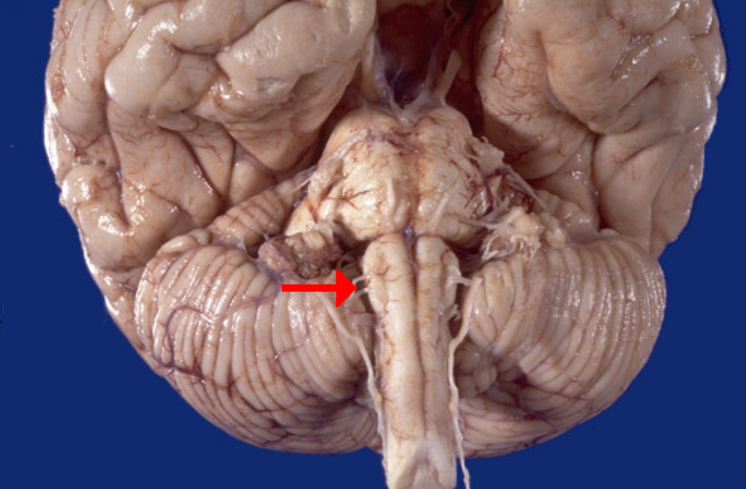

Label this cranial nerve

Hypoglossal (CN XII) nerve